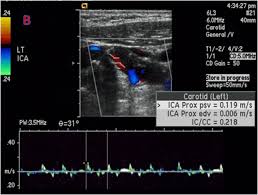

경동맥 초음파 검사는 고주파 초음파를 사용하여 목의 경동맥 혈관을 영상으로 확인하는 검사입니다. 혈관 내벽 두께, 혈류 흐름, 좁아진 정도 등을 실시간으로 볼 수 있으며, 조영제나 방사선 노출이 없어 안전합니다. 검사 시간은 약 20~30분 정도 소요됩니다.

경동맥의 협착 정도와 혈류 속도를 확인해 향후 뇌졸중 발생 가능성을 예측할 수 있습니다.

혈관 내막 두께, 협착 정도, 혈류 속도 등을 확인할 수 있으며, 결과에 따라 추가 정밀검사가 필요할 수 있습니다.